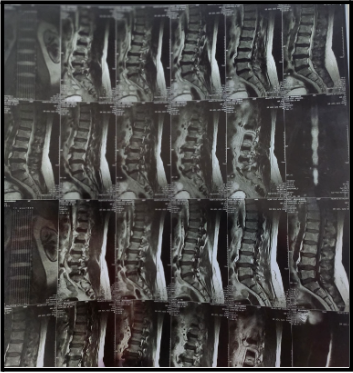

Since an MRI (Magnetic Resonance Imaging) produces incredibly detailed images of the soft tissues, nerves, and spinal discs, it is typically the first option. While piriformis syndrome may not directly cause changes in the spine, it may cause inflammation around the muscle area. On MRI, a herniated disc pressing on the sciatic nerve root will usually be seen.

This MRI reveals:

- No evidence of fracture, listhesis or generalized marrow abnormalities.

- However, diffuse posterior annular bulge of L3-4 intervertebral disc is causing compression of the thecal sac and indentation of lateral recesses.

- Circumferential bulge of L4-5 intervertebral disc causes compression of thecal sac, bilateral lateral recesses and indentation of transiting nerve roots along with moderate narrowing of the spinal canal.

- Right posterior para central bulge of L5-S1 intervertebral disc causes effacement of epidural fat

- Compression of right lateral recess & right transiting S1 nerve roots

- Moderate narrowing of CSF column is seen on MR myelogram

- Anterior & posterior osteophyte formation is seen at L3, L4 & L5